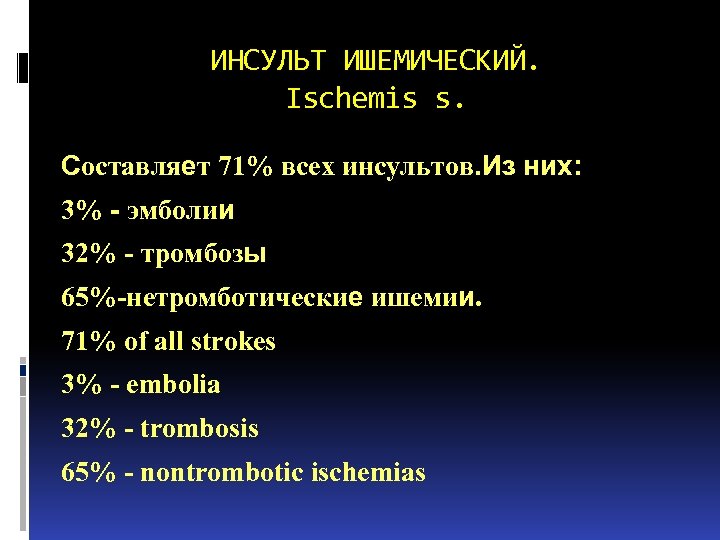

ИНСУЛЬТ ИШЕМИЧЕСКИЙ. Ischemis s. Составляет 71% всех инсультов. Из них: 3% - эмболии 32% - тромбозы 65%-нетромботические ишемии. 71% of all strokes 3% - embolia 32% - trombosis 65% - nontrombotic ischemias

ИНСУЛЬТ ИШЕМИЧЕСКИЙ. Ischemis s. Составляет 71% всех инсультов. Из них: 3% - эмболии 32% - тромбозы 65%-нетромботические ишемии. 71% of all strokes 3% - embolia 32% - trombosis 65% - nontrombotic ischemias